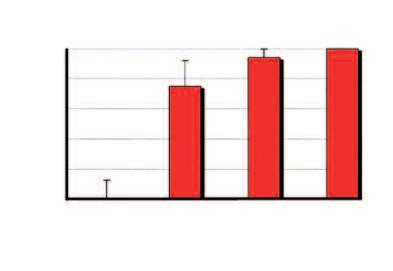

Aumento del numero dei decessi dovuti al cancro nei diversi gruppi di età, dal 1970 al 2000

Età dei pazienti 70 - 79 anni

Età dei pazienti 60 - 69 anni

Età dei pazienti 50 - 59 anni

Dati statistici per gli USA, dati comparabili per l’Europa. Fonte: Journal of the American Medical Association, 2005